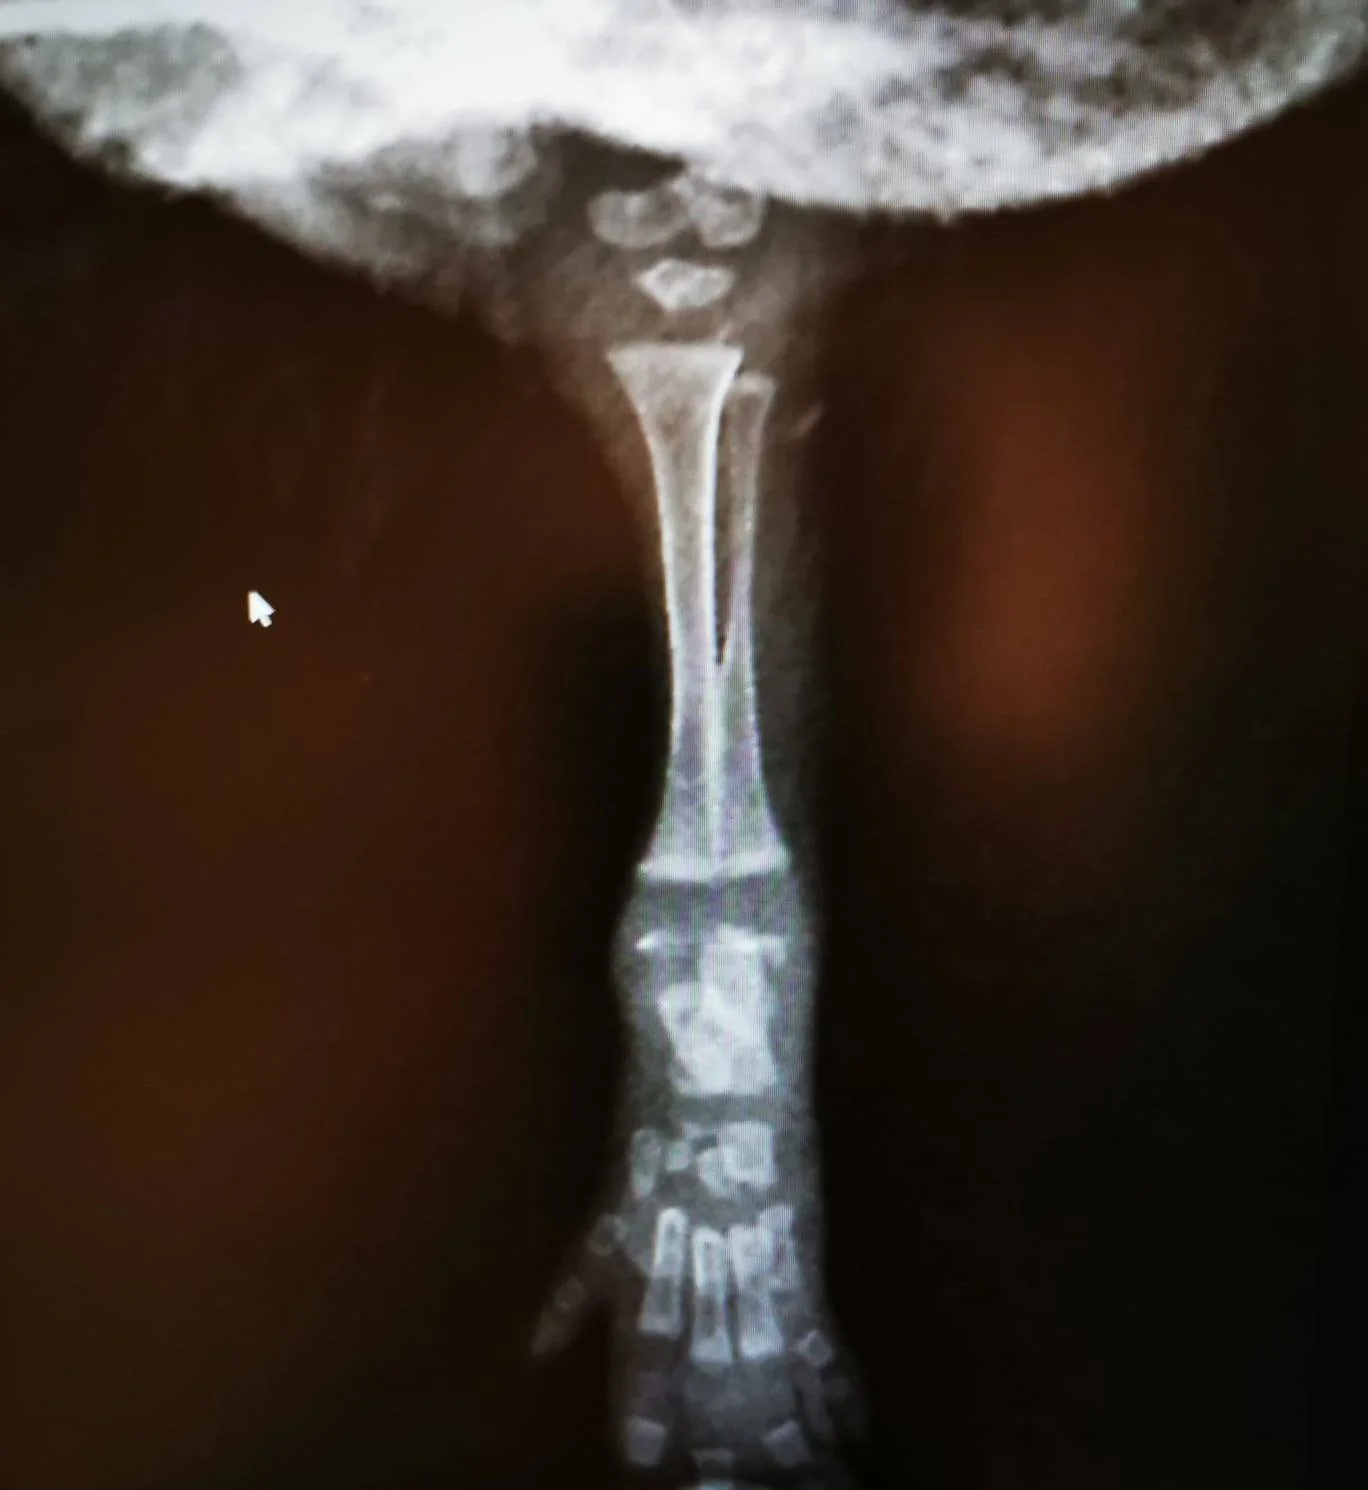

RX patte antérieure de hérissoneau